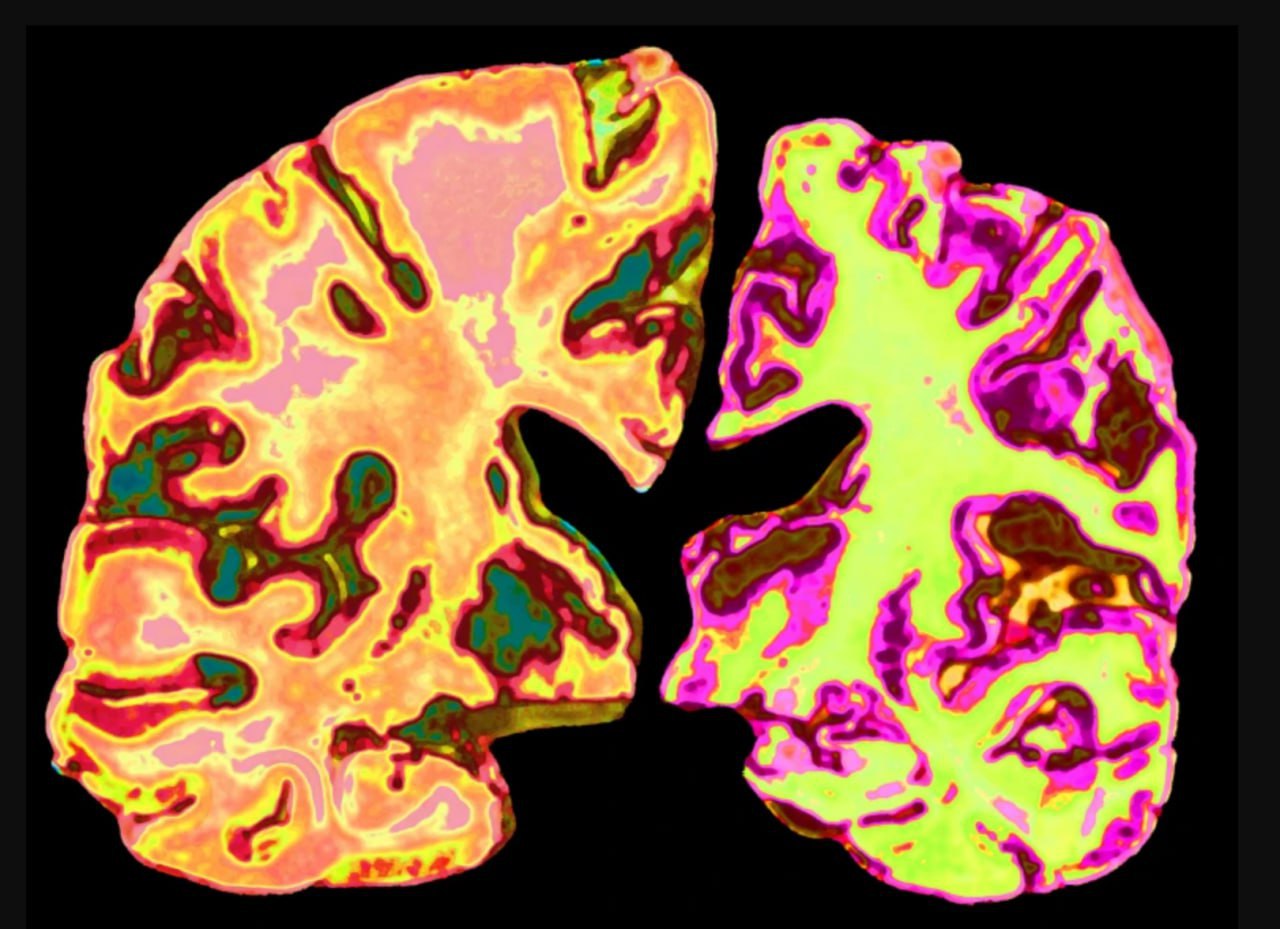

Науковці з’ясували, що у людей із легкими когнітивними порушеннями та діагнозом Альцгеймера рівень літію в мозку значно знижений. Цей висновок підтвердили під час аналізу тканин мозку та крові.

Результати вразили: тварини, що раніше втратили здатність запам’ятовувати та орієнтуватися, знову почали успішно виконувати тести на пам’ять. Крім того, в їхньому мозку зменшилась кількість амілоїдних бляшок і патологічних тау-білків, які вважаються головними маркерами Альцгеймера.